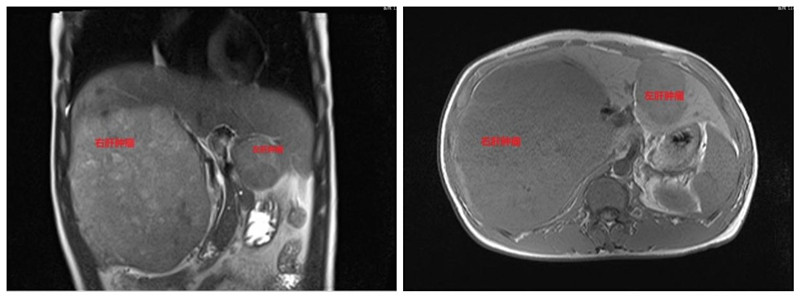

2024年10月13日,我院肿瘤科收到了患者家属送来的锦旗。事情追溯到2023年5月,一位30多岁的男性患者因发现肝占位入院,影像学显示“肝右叶见一大小约178mm×136mm×172mm肿物、肝左叶见一大小约66mm×47mm×69mm肿物”,AFP 12424.86 ng/ml,临床诊断原发性肝癌,因肿瘤巨大无法手术。患者家属非常悲观,找到科室副主任熊春主任医师说:“他才30多岁,上有老下有小的怎么办?一定要救救他”。

在科室主任沈永奇主任医师的带领下,肿瘤科团队对患者进行个体化的处置:先予HAIC术(经皮肝动脉置管持续灌注化疗术),待肿瘤缩小后再行TACE术(经皮肝动脉置管灌注化疗栓塞术),残余病灶予适形调强放疗。到2024年6月患者复查影像学显示肿瘤明显缩小,“右肝肿物最大径线约76mm×61mm、左肝肿物最大径线约21mm×16mm”,AFP 5.62 ng/ml。